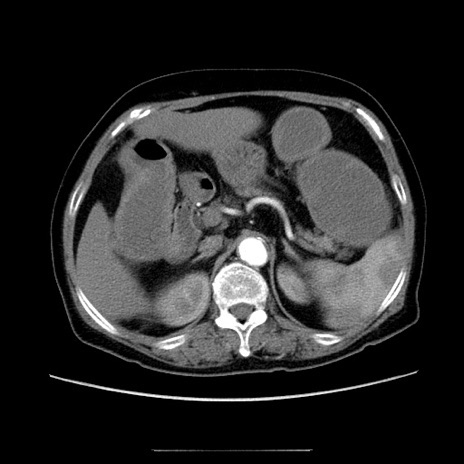

症例5(横断像)

【症例】70歳代女性

【主訴】お腹が張る

【現病歴】1週間くらい前から腹部膨満の自覚あり。昨日夜から増悪したため、本日救急外来受診。

【身体所見】意識清明、BT 36.5℃、BP 165/106mmHg、HR 80bpm、SpO2 98%、腹部:膨満、軟、自発痛・圧痛なし、触診にて不快感あり、腸蠕動音:減弱

【データ】WBC 12600、CRP 1.04